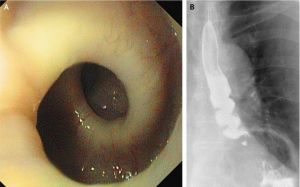

2.食管X線鋇劑造影

胡桃夾食管的食管X線鋇劑造影可以正常或提示有非特異性食管運動功能障礙,對診斷胡桃夾食管缺乏特異性,但對除外食管器質性和其他功能性的異常病理改變有重要意義。